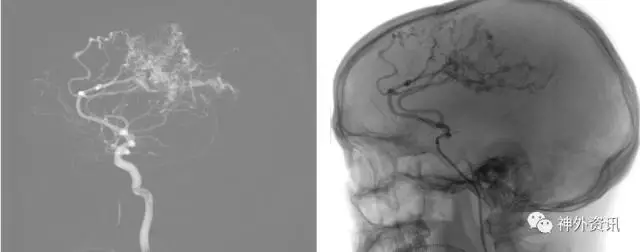

(Envoa DA导引导管—左侧颈内动脉海绵窦段)

(瘤1:单纯弹簧圈栓塞致密,动脉瘤不显影)

(瘤2:支架辅助弹簧圈栓塞致密,动脉瘤不显影)

(术后3D双容积重建和Dyna CTA)